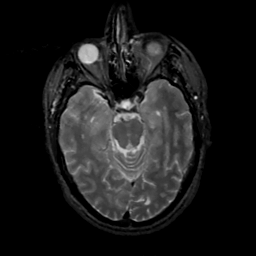

MR Study #15, June 9, 1991 -- Slice #18

[Home][Help][Clinical][Tour 1][Tour 2] Slice 18